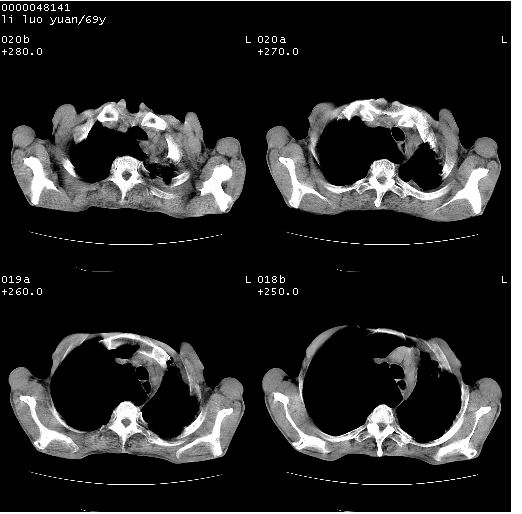

临床资料:老年患者,咯血、消瘦

影像表现:桶状胸,双肺纹理纤细、紊乱,透过度增高,肺野内可见多发、散在、大小不等的无壁高透过影,右肺中叶外侧段分叶样软组织占位,左上肺纤维索条样密度影,相应层面左侧胸腔轻度萎陷,纵隔左移。

影像诊断:1、慢支、肺气肿、双下肺野肺大泡形成

2、左上肺陈旧性肺结核

3、右肺中叶外侧段占位 考虑肺ca可能性较大、建议增强及痰检脱落细胞